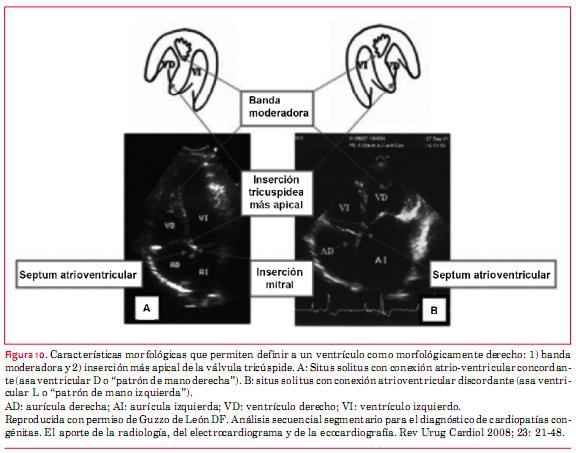

Esta anomalía, antiguamente denominada “inversión ventricular”, puede presentarse en situs solitus o inversus y consiste básicamente en la presencia de doble discordancia (atrioventricular y ventriculoarterial). De modo que la sangre proveniente de las venas cavas llega a la AD y de esta cavidad a un ventrículo morfológicamente izquierdo. Del ventrículo morfológicamente izquierdo emerge la arteria pulmonar y por ello la circulación está fisiológicamente “corregida”. En recirculación, las venas pulmonares vierten su sangre en la aurícula izquierda (AI) que aboca en un ventrículo morfológicamente derecho del cual emerge la aorta. El diagnóstico ecocardiográfico de esta anomalía requiere el conocimiento del análisis secuencial segmentario(16). Básicamente debe saberse que los ventrículos se definen ecográficamente estrictamente por su morfología. El VD es el que tiene la banda moderadora y su válvula auriculoventricular (AV) (tricúspide) presenta una inserción más apical (figura 10)(16).